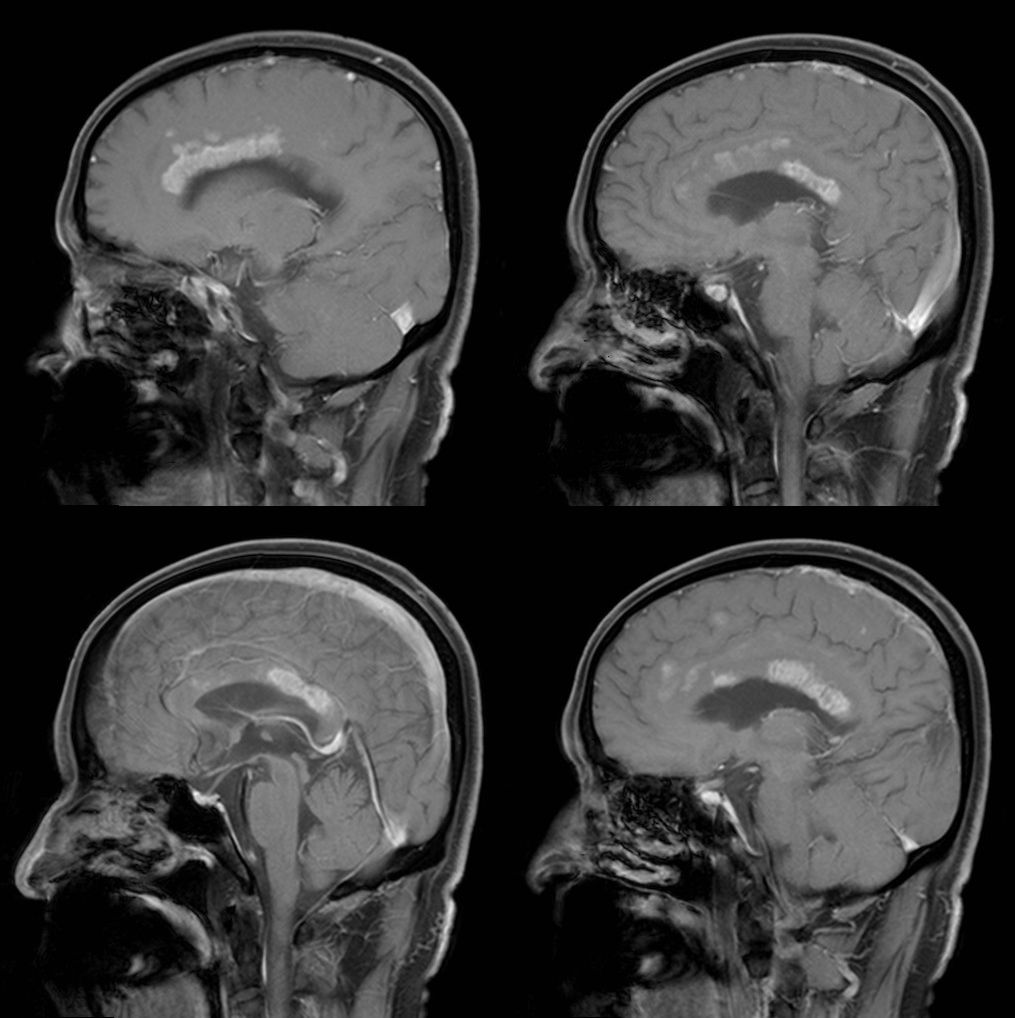

•随着病变进展至亚急性期和慢性期,胼胝体内可出现坏死、囊变,以膝部及压部表现为著。在膝部和体部常表现为中心夹层状异常信号,类似“三明治”状,其境界清楚,据认为这是本病的特点之一。病理检查证实,病变主要对称性侵及胼胝体的中心层,而背、腹层面的组织结构相对完好。主要的组织学所见为脱髓鞘,少突胶质细胞明显减少,而含脂巨细胞大量增多。部分病例在T2加权像上,偶见胼胝体变性、坏死区内出现极低信号,镜下病理显示含脂巨细胞内可见散在或成堆的含铁血黄素分布,可能为T2异常低信号的病理基础。

上排:原发性胼胝体变性急性期

下排:原发性胼胝体变性慢性期,表现为胼胝体萎缩、软化

急性期原发性胼胝体变性(胼胝体压部及体部病变,CT呈低密度,T1WI呈稍低信号,FLAIR呈稍高信号,扩散受限)向慢性期转变,慢性期胼胝体压部病灶出现坏死或囊变,FLAIR呈低信号